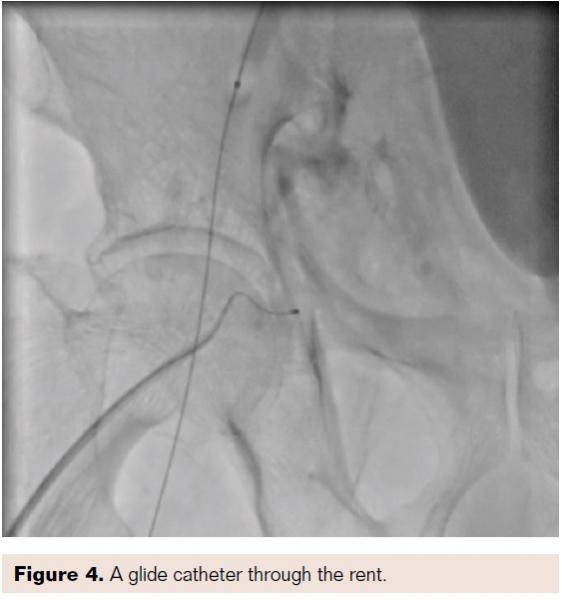

A glide catheter 4 Fr was threaded over the guidewire, and gel foam mixed with contrast was injected into the aneurysmal sac (Figures 4 and 5).

Details of how to embolize the femoral artery rent with gel foam: We used the antegrade approach. Abgel absorbable gel foam (Sri Gopala Krishna Labs) is a sterile, hemostatic, absorbable gelatin-based foam that is specially prepared for surgical use. Two 80 x 50 x 10 mm pieces of Abgel were scraped into tiny pieces with a sterile scalpel and mixed with about 1-3 mL contrast; 0.5 mL of this solution was then injected through the microcatheter/glide catheter into the rent. Prior to this, a little contrast was injected into the microcatheter to ensure the tip of the glide catheter was outside the femoral artery and the contrast was flowing only into the subcutaneous space. The 0.5 mL of gel foam/contrast mixture was then injected and a cine loop image was obtained.